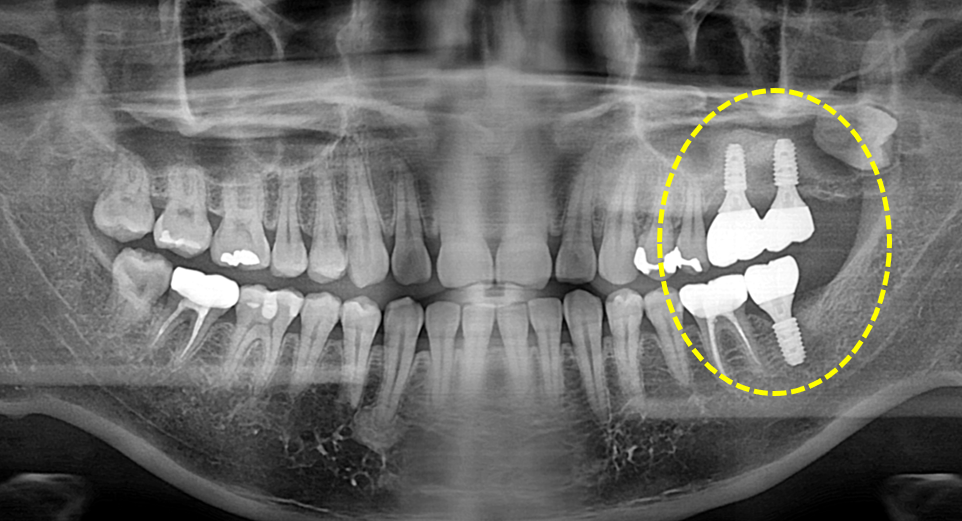

상악동 거상술을 동반한 임플란트 보철.

치주염으로 인해 치조골이 많이 소실된 상태라고 하더라도 상악동 거상술을 동반한

치조골 이식을 통해 임플란트 뿌리 기둥을 고정하고 보철을 완료할 수 있습니다.

정확한 위치와 적절한 깊이에 임플란트를 식립함으로써

보철 후 부작용을 줄일 수 있습니다.